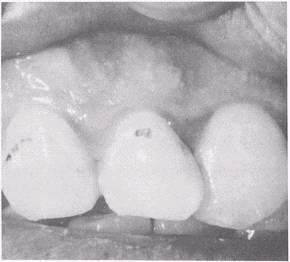

Dental caries usually appear first as a chalky white spot on the enamel, which indicates the decalcification process. If proper oral hygiene is not maintained, the lesion may become stained and take on a dark appearance. In pit and fissure caries, the area of decalcification at the surface is normally small, and the white spot is less noticeable than in smooth surface caries. In either type of caries, the surface becomes roughened, as can be noted by passing a dental explorer point over it. If the tooth surface has an area that has not progressed past the decalcification stage, this type of carious lesion is called incipient. As the decay spreads in the enamel, it may stop. If this occurs, the process is called an arrested carious lesion (fig. 5-5). These areas in which dental caries have been arrested are dark and, in some instances, hollowed out. A dental explorer passed over or in these areas will feel hard to the touch. If the area still has active decay, the explorer may "sink in" the soft decay.

Figure 5-5.\Arrested caries.